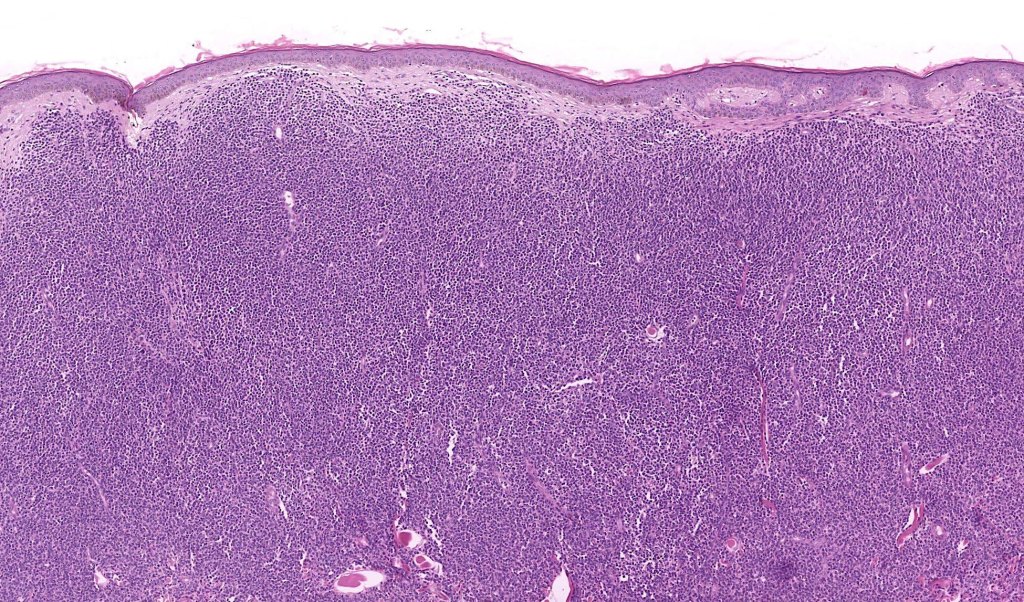

Histological features

. No epidermal involvement

. Dermal +/- subcutaneous fat infiltrate

. No angioinvasion or angiodestruction

. Monotonous blast cells with gray-blue cytoplasm & irrregular vesicular nuclei with prominent nucleoli